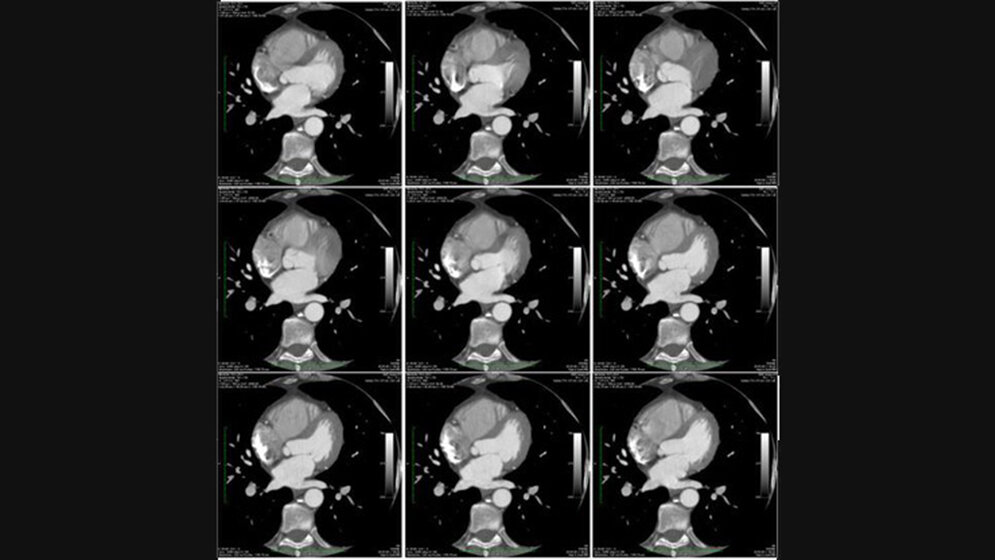

Abb. 18: Beispiel für die Abbildungsschärfe der Koronargefäße zu verschiedenen Zeitpunkten des Herzschlages A. Riemer

Nach der Patienten- und Untersuchungsvorbereitung folgt nun die strukturierte Untersuchungsdurchführung. Auch hier empfi ehlt sich die strukturierte Vorgehensweise. Lernen Sie wie Sie Kardio-CT Untersuchungen (Calcium Score und Kardio-CTA) planen und welche Scantechnik sich für die unterschiedlichen Patienten besonders gut eignet. Darüber hinaus fi nden Sie Tipps, die Ihnen die Arbeit bei der Wahl der besten Rekonstruktionsphase erleichtern.